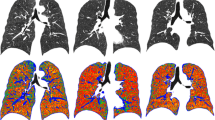

Emphysema

We performed a quantitative assessment of lung emphysematous changes with densitometry in images reconstructed with the smooth (b31f Siemens) kernel. For such a purpose, we used the Pulmo (Siemens, Healthcare) software in the Florence cohort and the SYNAPSE 3D (Fujifilm) software in the Pisa cohort, according to an established procedure [17]. The presence of emphysematous changes was defined using the 6.0% threshold of the relative area of the lung with density values below 950 Hounsfield units (RA950) [18] normalized to the lung volume at acquisition. Subjects with emphysematous changes were then arbitrarily divided into those with mild (6% ≤ RA950 ≤ 9%) and those with moderate-severe (RA950 > 9%) emphysema.

Machine learning analysis (Fig. 1) showed that RA950 was the best single feature for the prediction of overall and CVD mortality among age, gender, pack-years, smoking status, and CAC visual score, with AUROC values of 0.70 for overall and 0.73 for CVD mortality. For the prediction of LC mortality, the two most important features were pack-years and RA950, with AUROC = 0.61.